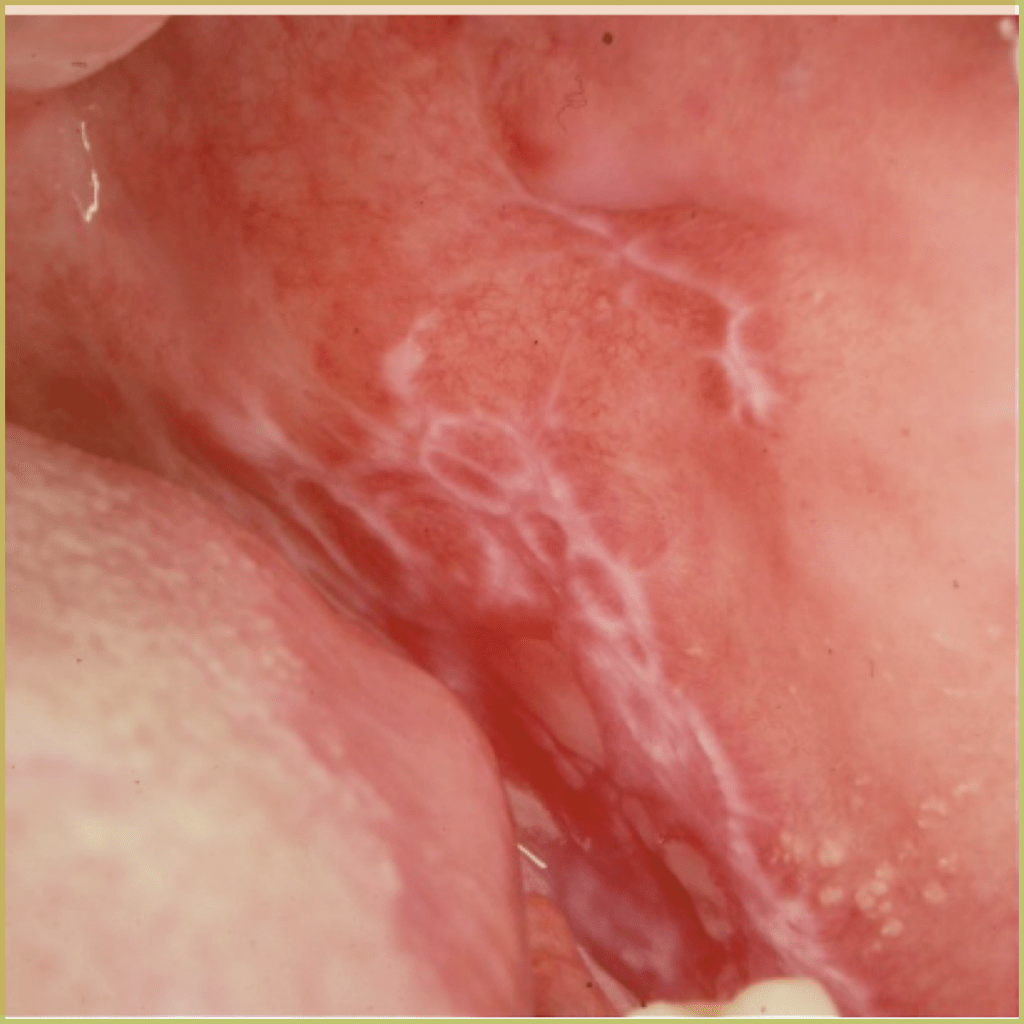

LICHEN PLANUS

Lichen Planus (Wickham striae) is a chronic inflammatory autoimmune disease that can affect the skin, nails, hair and mucous membranes. Oral lichen planus affects 3-4% of the population and is typically characterized by the presence of distinct reticular white lesions. The cause is not well understood but thought to involve the targeting of basal keratinocytes by activated T Cells. Clinical variations include erosive/ulcerative, papular, plaque-like, atrophic and bullous lesions. Multiple types may be found in the same patient and even in the same lesion. The common clinical presentation includes:

- Asymptomatic reticular lace-like patterns is the most common appearance.

- Most often located on the buccal mucosa, then tongue, gingiva and lips.

- Bilateral, often symmetrical distribution.

- Erosive or atrophic pattern can present with symptoms (pain or burning)

- Extra-oral lichen planus may accompany oral presentation (planar (flat-topped), purple, polygonal, pruritic, papules, and plaques).

- Higher incidence in white females and more likely in the fourth to eighth decade.

Diagnosis is based on the lesion history, clinical presentation and microscopic findings, which may include:

- Hyperkeratosis.

- Liquefactive degeneration of the basal layer of the epithelium.

- Presence of Civatte bodies (apoptotic keratinocytes).

- Band-like appearance of inflammatory infiltrate (lymphocytes) in the mucous membranes beneath the epithelium.

- No epithelial dysplasia.

- Saw tooth rete ridges.

Your differential diagnosis should include:

- Lichenoid drug reactions.

- Lupus erythematosus.

- Mucous membrane pemphigoid.

- Erythema multiforme.

- Contact stomatitis.

Reticular oral lichen planus does not require treatment and does not progress to a more serious disease. For symptomatic lesions, immune-suppressing agents can be utilized. Treatment options include:

- Topical corticosteroids for mild to moderate cases.

- Systemic prednisone for more severe cases.

- Topical tacrolimus ointment.

Though treatment does not provide a cure, long term control can be established. The prognosis is generally good with very rare malignant transformation.